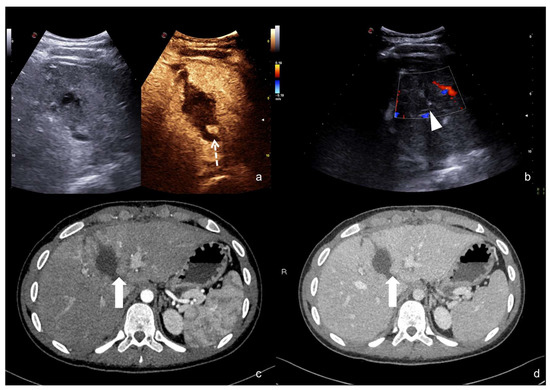

- Contained vascular injuries:

Contained vascular injuries include pseudoaneurysms and arteriovenous fistulas. Pseudoaneurysms are focal outpouchings of the external vessel contour due to the partial disruption of the wall, which is contained by the tissue around the vessel (Figure 18, Figure 19 and Figure 20) [1,30].

Figure 18.

Admission CT (a) and follow-up CEUS (b) of the spleen of the same patient as Figure 14. At admission CT, in the arterial phase, was noticed a small hilar pseudoaneurysm (a, arrow). CEUS was performed after the embolization, showing the lack of vascular enhancement in the pseudoaneurysm site (b, arrow). Adopted from ref. [30], 2021, Iacobellis, F.; et al.

Figure 19.

High grade traumatic splenic injury with vascular complication. Arterial (a) and venous (b) phase CEUS examination in a 25−year-old patient admitted at the emergency department for blunt abdominal trauma, showing multiple splenic lacerations and a voluminous arteriovenous fistula (white arrowhead). Subsequent arterial (c) and portal vein (d) phase contrast-enhanced CT scan further confirmed the diagnosis (black arrowhead).

Figure 20.

CEUS (a) of a 23−year-old man referring to the emergency department for direct blunt trauma to the right flank showed the presence of a small pseudoaneurysm (white arrow) inside the contusion area of the right kidney; the diagnosis was then confirmed at the axial arterial phase contrast-enhanced CT scan (b), as well as at angiography performed for treatment purposes (c).

Arteriovenous fistulas consist of traumatic communication between the arterial and venous systems [1,30]. Fistulas are characterized as asymmetrical, early contrast opacification of a vein during the early arterial phase of the study (Figure 21).

Figure 21.

Companion case of Figure 2b. Renal arteriovenous fistula (white arrowhead) at color–Doppler US (a) and CEUS (b), confirmed (c) at contrast-enhanced CT scan (arterial phase, coronal MIP reconstruction) and subsequent angiography (d).